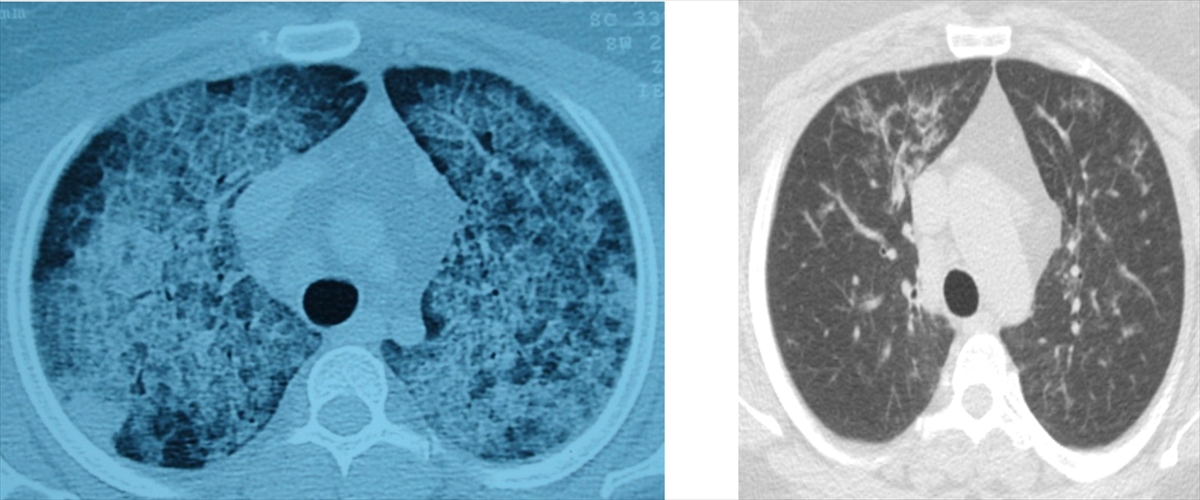

Akciğer yıkaması yöntemiyle hastalar yeniden rahat nefes alıyor